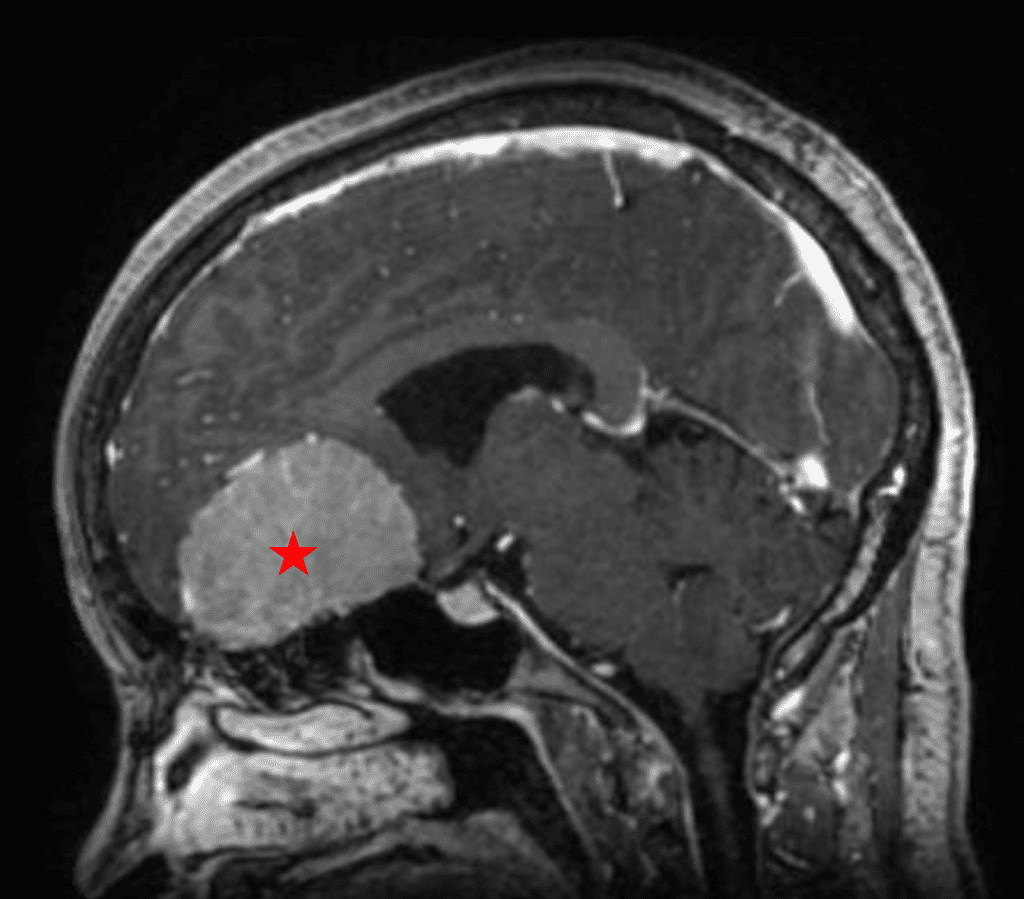

This is a 49-year-old otherwise healthy female who presented with bifrontal and retro-orbital headaches, behavioral changes, and forgetfulness. Symptoms have been progressively worsening over the past month. Her neurologic exam revealed a pronator drift, otherwise was unremarkable. MRI brain demonstrated a large extra-axial homogeneously enhancing mass of the anterior cranial fossa, resulting in significant mass effect and vasogenic edema (Figure 1a and 2a). Imaging was most consistent with a planum sphenoidale meningioma. She was referred to Dr. Xavier Gaudin for neurosurgical evaluation.

Figure 1a – Preoperative MRI demonstrating an extra-axial enhancing mass of the anterior cranial fossa.

Figure 2a – Preoperative MRI demonstrating an extra-axial lesion with surrounding vasogenic edema and mass effect on the frontal lobes.